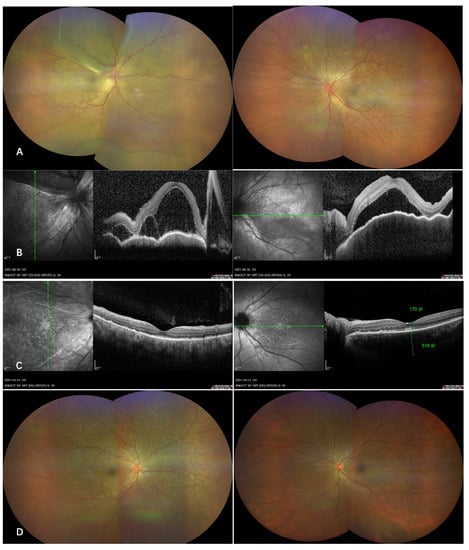

A previously healthy 57-year-old female presented to our clinic with complaints of bilateral blurred vision 10 days following the first dose of inactivated vaccine (Sinopharm) and again got severe visual loss in the right eye 2 days after the second dose of vaccination (Sinovac). On examination, the visual acuity was hand motion OD, and 0.25 OS and the intraocular pressures were 11.2 mmHg OD and 11.3 mmHg OS. An anterior segment examination revealed a conjunctiva congestion, gray fine keratic precipitate, and anterior chamber cell in both eyes. The dilated fundus examination showed multiple serous retinal detachment (Figure 2), which was consistent with intraretinal and subretinal fluid, shown on OCT Figure 2B. Tests for HIV, syphilis and tuberculosis were negative. The patient was diagnosed with VKH, and systemic steroids were initiated. Visual acuity improved to 1.0 in both eyes with resolved subretinal detachment (Figure 2C,D).

Figure 2. Acute onset of Vogt–Koyanagi–Harada disease after administration of inactivated COVID-19 vaccine. Wide-field color fundus photography of a previous healthy woman who developed bilateral multiple serous retinal detachment 10 days following the first dose of the Sinopharm inactivated COVID-19 vaccine (A), corresponding to the OCT revealing intraretinal and subretinal fluid (B). The patient started on oral steroid with tapering dose, and the bullous retinal detachment resolved completely after 6 weeks of follow-up (C and D).